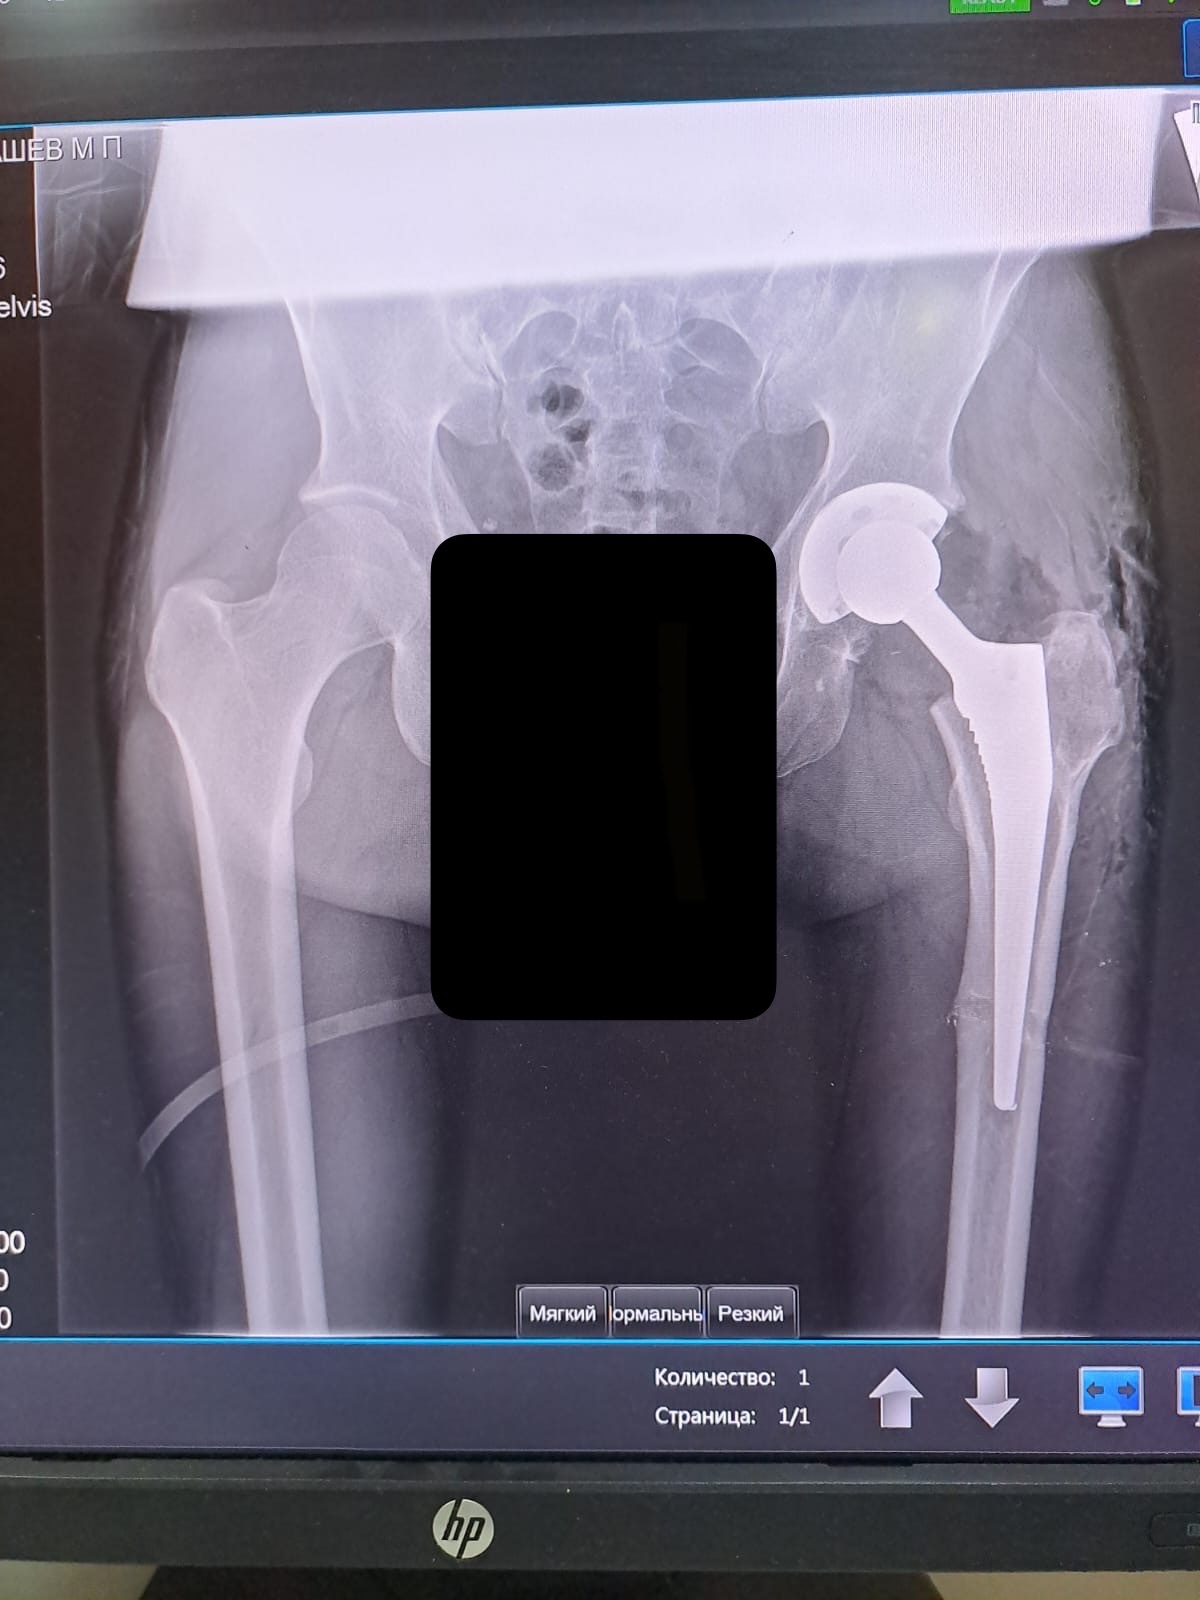

Прошло 13 лет, в мае 23-года заболело очень бедро. В поликлинике записался к травматологу, была очередь полтора месяца. Пошел в платную, сделал КТ,вердикт- надо менять тазобедренный сустав. Сделали 2 блокады, укололи гилауроновую кислоту(16,5 тысяч лекарство,хм..(() кому то она не помогает, у меня боль ушла на 5 месяцев. Пришло время травматолога, получаю у него направление к врачу, который делает эти операции. Рентген и к нему. И печаль-после удаления пластины, которая скрепляла разрушенную шейку бедра, остался винт.

Его нужно удалить, у нас в городе это не делают. Дал направление на это дело и я поехал в соседний город. Это был август. Операцию сделали в конце октября. Три месяца я собирал справки и туда-сюда по ездил. При операции был укол в спину, меня положили на бок и я видел фоторенген. Сверлили шуруповертом два молодых паренька, делали фотки, и я видел как уходит из меня этот кусочек винта. Он был поперек тазобедренной кости, что мешало установке сустава.

Теперь появляется у меня трость. Уехал к себе, записался к первому моему травматологу, тк к «тому самому» нужно записываться по направлению от первого. В декабре к нему попал-суставов нет, перед Новым годом не появятся, вот тебе мой номер телефона-будем держать связь. Два месяца ничего не происходит. В конце февраля он мне дал листик с нужными анализами-потихоньку сдавай, говорит, но суставов еще нет. Все сдал за 2 недели, апрель-суставов нет, май-назначили операцию на 3.06. Ура!! Приехал на госпитализацию со всеми вещами-суставы не пришли, а должны были, ты пока обнови все анализы, на конец июня тебе госпитализация, но не факт , что они придут. Обновляю все, приезжаю 25.06 - суставов нет. Жизни нормальной нет, работы нормальной нет, в середине июля сообщение от врача-хватай все и 21.07 ложишься уже точно(притом в воскресенье). Свершилось-я лег. В понедельник сделали операцию:укол в спину, шуруповерт, болгарка, молоток, запах костей(как у стоматолога, когда он тебе зубы сверлит). Был зажат в тиски-больно очень, хоть и наркоз. Укол морфина был после операции и в каждую последующую ночь- 4 раза. Очень счастливый финал, сустав состоит из титана, хрома, кобальта, ванадия, тоесть он пожизненный, его менять не нужно(боюсь представить его цену). Поэтому это дело так затянулось. Все по ОМС. Ноги еще выровнялись(больная была короче на 2см).

Выписали в четверг, тоесть на третий день после операции. Три месяца реабилитации, нельзя допускать угол менее 90 градусов между телом и бедренной костью, носки, обувь сам не одену. Огромное спасибо моему врачу - Цвирко Александру Сергеевичу, Ливадийская городская больница. Я вам благодарен, за то что вложили в меня свои силы.